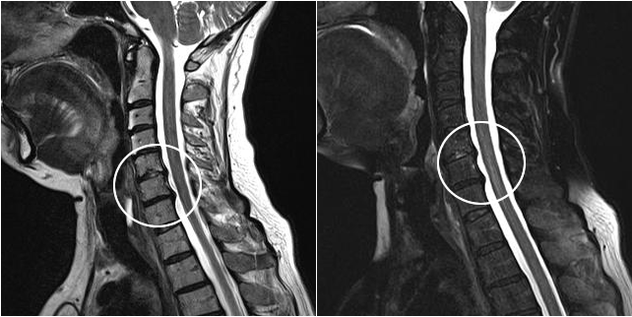

Diagnostiko-metodo modernoen artean, MRI eta CT daude, kartilagoaren eta hezur-ehunaren suntsipen-prozesuak zehatzen aztertzea ahalbidetzen dutenak. Gainera, teknika hau erabiliz, gaixotasunaren iturritik gertu herniak eta beste ehun bigunen akatsak diagnostikatzea komeni da.

Trápaga osteokondrosia MRI irudian